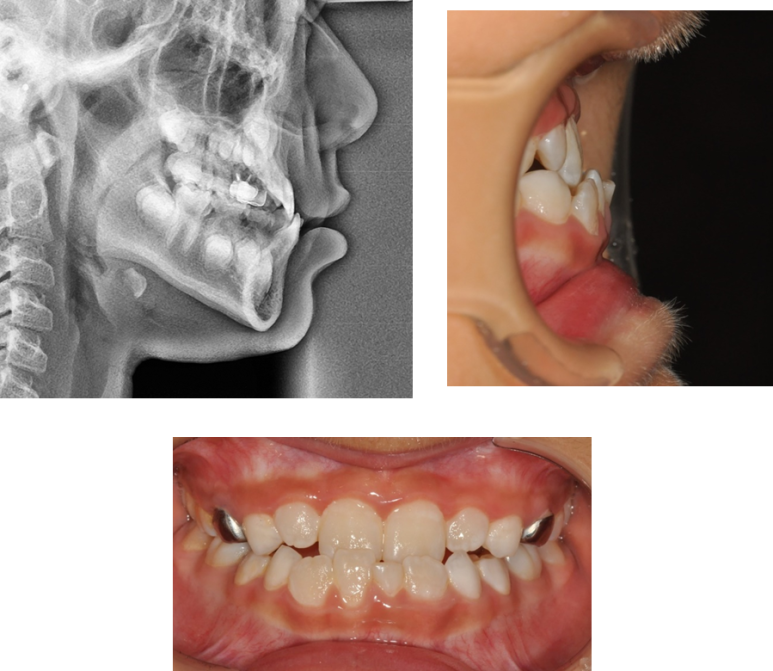

그러면 이렇게 반대교합도 해소하고,

위 아래 턱의 조화도 맞출 수 있게 되었습니다.